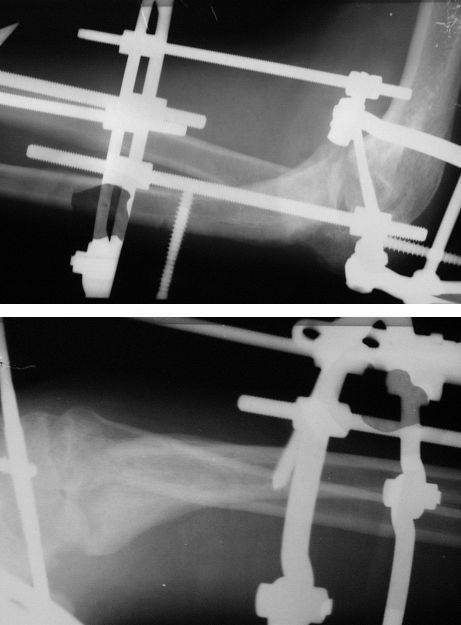

Коллеги! Сделана операция. Убрана рубцовая ткань, освежены концы до "кровяной росы", произведен релиз локтевого отростка и заднего отдела сустава - прошел до венечного отростка. После адаптации отломков выяснилось, что полное сопоставление происходит только на 1/4 периметра. Уложены аутотрансплантаты взятые из крыла подвздошной кости. Приведена схема. Через локтевой отросток проведены две спицы с упорными площадками с разбросом в 1 см, закрепленные на отдельном полукольце. Дана компрессия. Пятые сутки, рана заживает первичным натяжением. Выписываю. На 14 сутки буду пробовать движения.

Николай.